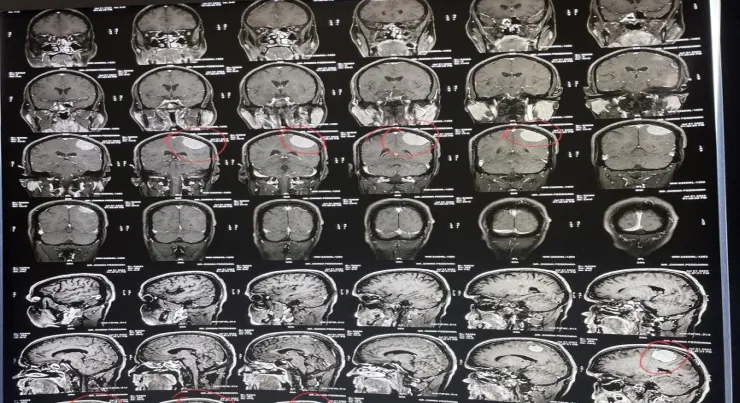

This month we would like to share a case of a 52-year-old gentleman who presented with severe headache, tingling and numbness over the right half of the body. He was evaluated with an MRI of the Brain which showed an Extra axial heterogenously enhancing lesion in the left parietal region. The dimensions of the lesion were 4.5x4.1x3.8 cms (ApxCCxTr) and had a broad attachment with the adjacent dura. It was compressing the adjacent brain parenchyma.

We operated on him under General Anesthesia, a left Parietal Craniotomy was done and the dura overlying the tumor was gently laid open and dissected away from the tumor. To our surprise, on the table the tumor was highly vascular had no clear margins contradicting the MRI findings. So our anaesthesia team started a blood transfusion and the surgical team gradually moved to a piecemeal approach and excised the tumor. A near total excision was achieved and the cavity was packed with hemostatic agents as there was profuse bleeding towards the end of dissection.